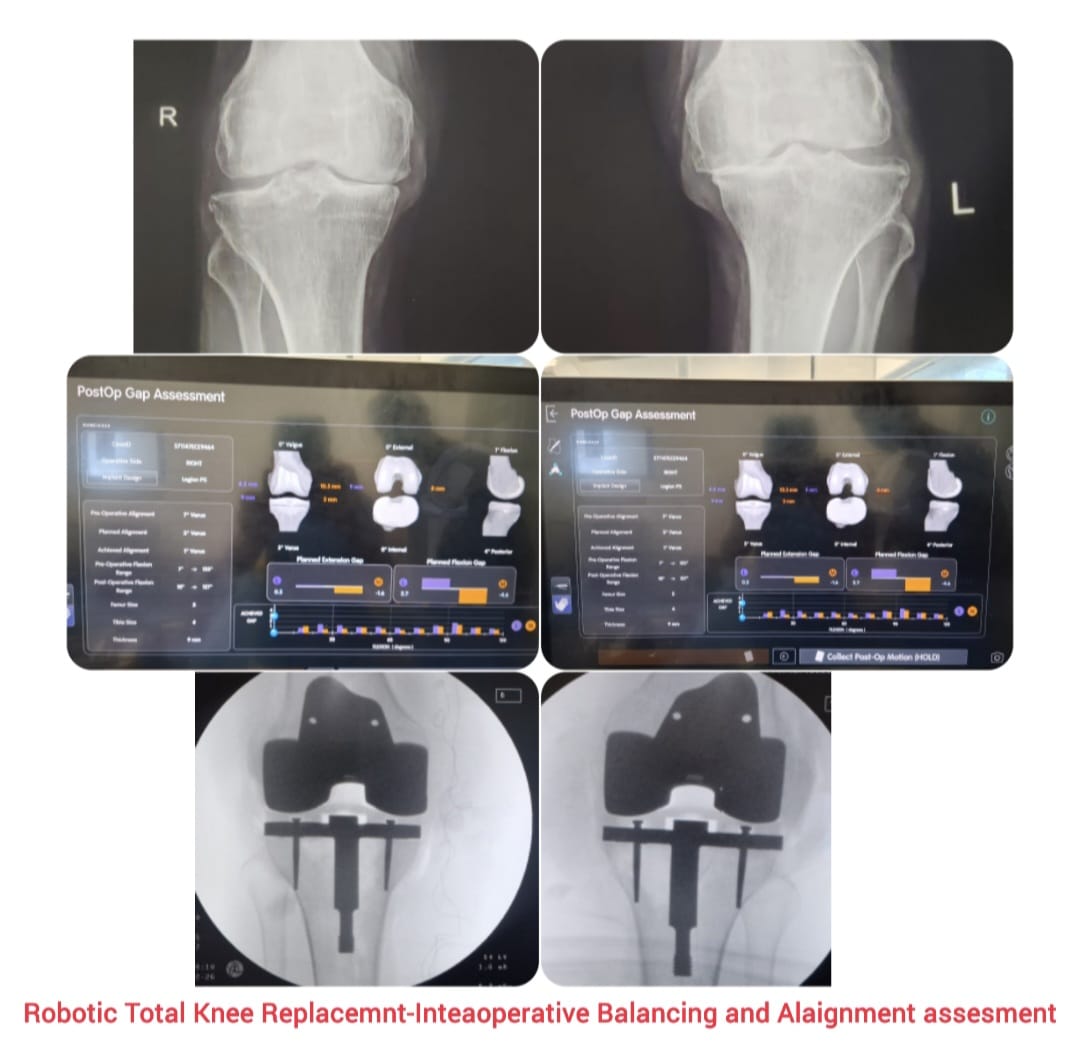

Knee replacement, also known as knee arthroplasty, is a surgical procedure performed to relieve chronic knee pain and restore joint function in patients suffering from advanced arthritis, severe joint damage, or deformities. The procedure involves replacing damaged cartilage and bone surfaces with durable artificial implants that restore smooth knee movement.

Knee arthroplasty is carefully planned based on the patient’s age, activity level, degree of joint damage, and overall health. Modern surgical techniques and advanced implant designs allow improved alignment, stability, and long-lasting outcomes with reduced postoperative discomfort.